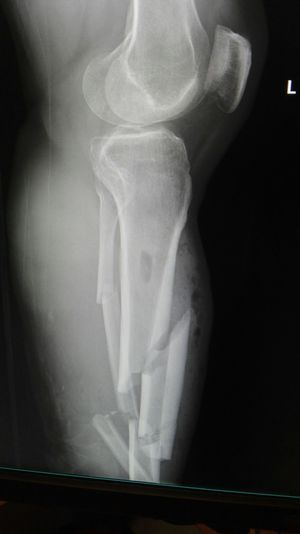

Xray

Fracture

Accident

Leg

Motorbike